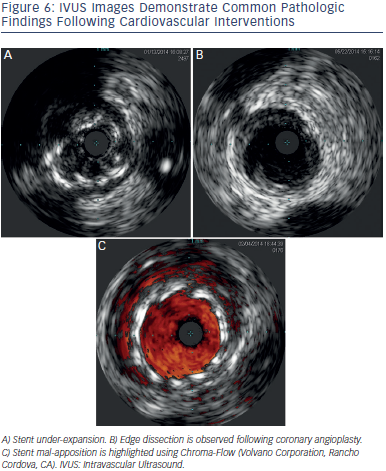

Pre-intervention vessel size, lesion length and morphology are evaluated to select the appropriate strategy and stent size and length. Post-intervention stent landing, expansion and apposition are evaluated. Complications are excluded (e.g. malapposed or under-expanded stents, geoImage titlegraphic miss, dissections, plaque prolapse, residual thrombus), and fine tuning performed. Figure 6 demonstrates some post intervention issues encountered during IVUS.